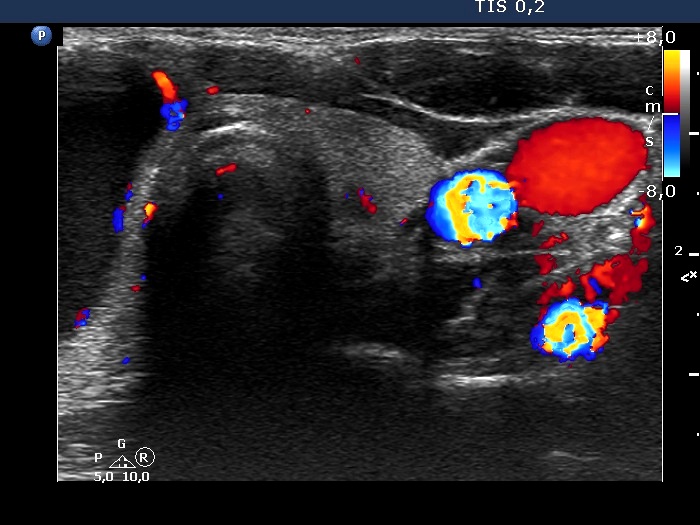

Right lobe, longitudinal scan

Left lobe, transverse view, color Dopple mode. The vascularization is not specific.